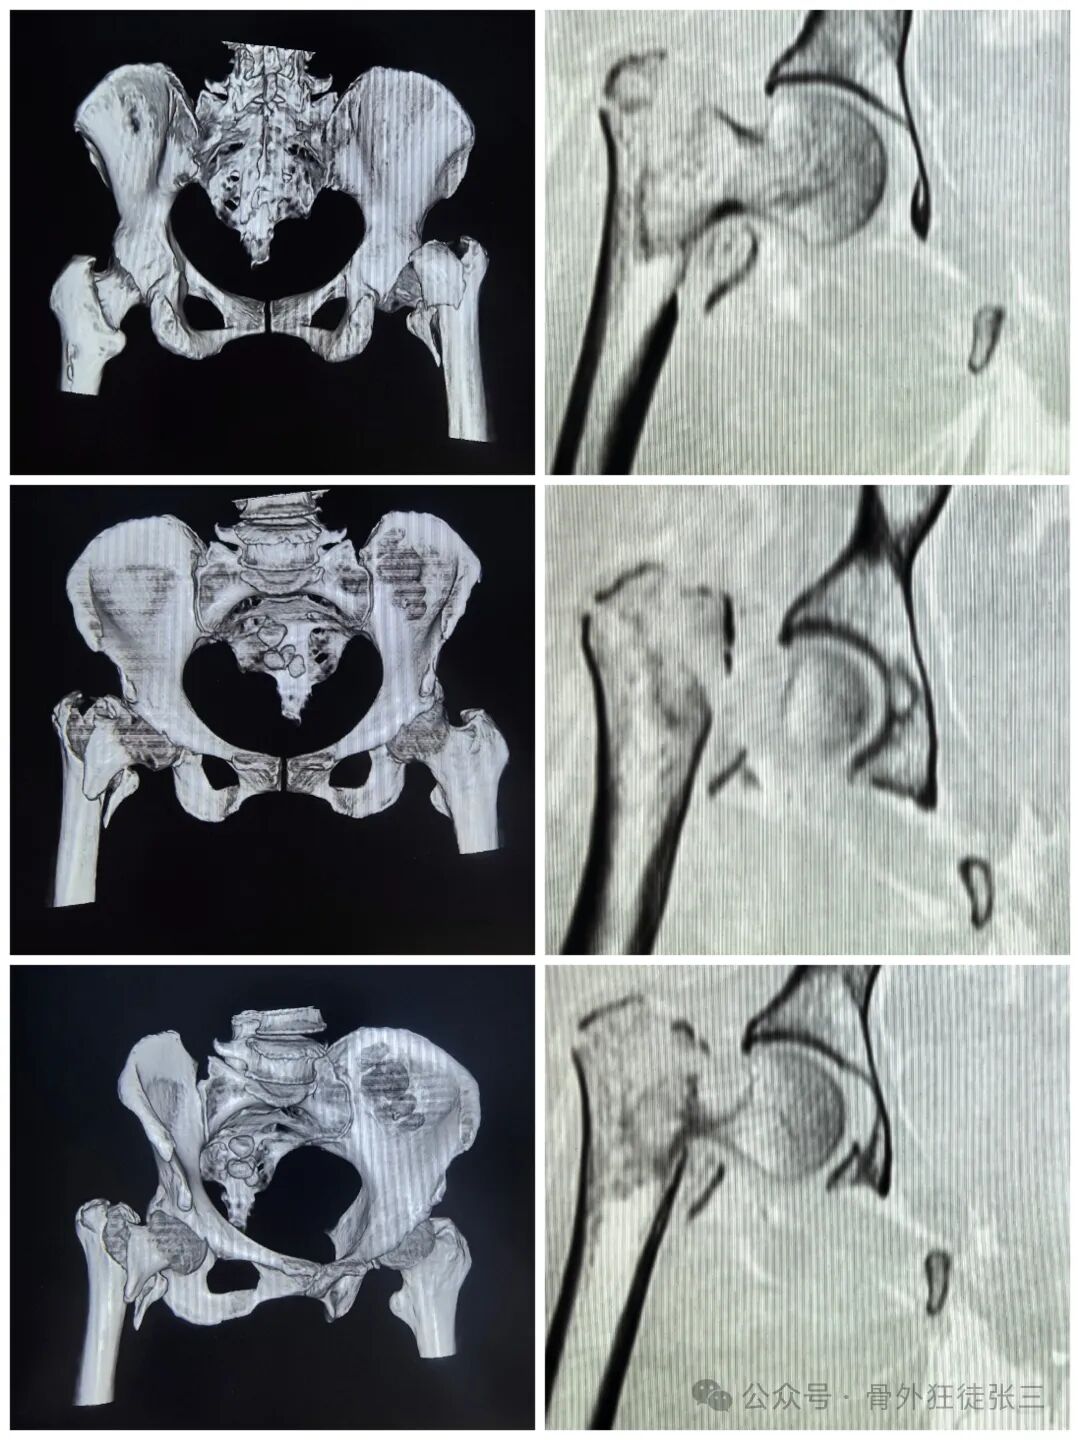

【检查】:

【临床诊断】:

右转子间骨折(A2.2)

再次透视

正位复位满意

导针正位中下1/3

骨钩过牵了

有点阴性支撑

侧位导针居中

术后正位

进针点都是碎的

内移失败

瑕疵

内侧有个皮质骨块

内移动进针点说不定主钉插入时就可复位了